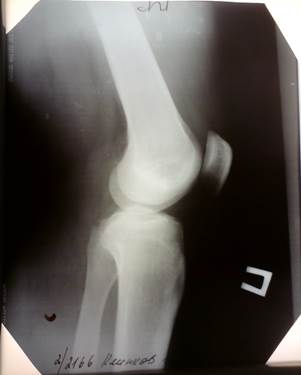

Рентгенограмма правого коленного сустава в двух проекциях от 22.09.2010г.:

Форма сустава не изменена. Контуры четкие. В боковой проекции наблюдается затемнение костных структур, в связи с отеком. Межмышечные пространства расширены, в связи с отеком мягких тканей.

Боковая проекция Прямая проекция

4) результатов дополнительных методов исследования: Рентгенограмма правого коленного сустава в двух проекциях от 22.09.2010г.: форма сустава не изменена. Контуры четкие. В боковой проекции наблюдается затемнение костных структур, в связи с отеком. Межмышечные пространства расширены, в связи с отеком мягких тканей.